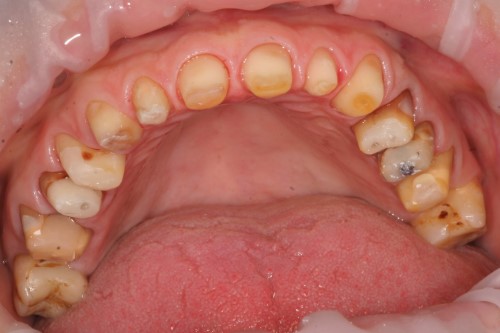

Nagrania z gabinetu dra n. med. Marcina Krywulta rejestrujące szczegóły jego pracy klinicznej z udziałem pacjentów na różnych etapach leczenia (od preparacji wertykalnej zębów, poprzez wykonanie i osadzenie prowizorium, po procedury przymiarki i zacementowania koron).

7. Prezentacja video z gabinetu: Preparacja wertykalna zębów krok po kroku.